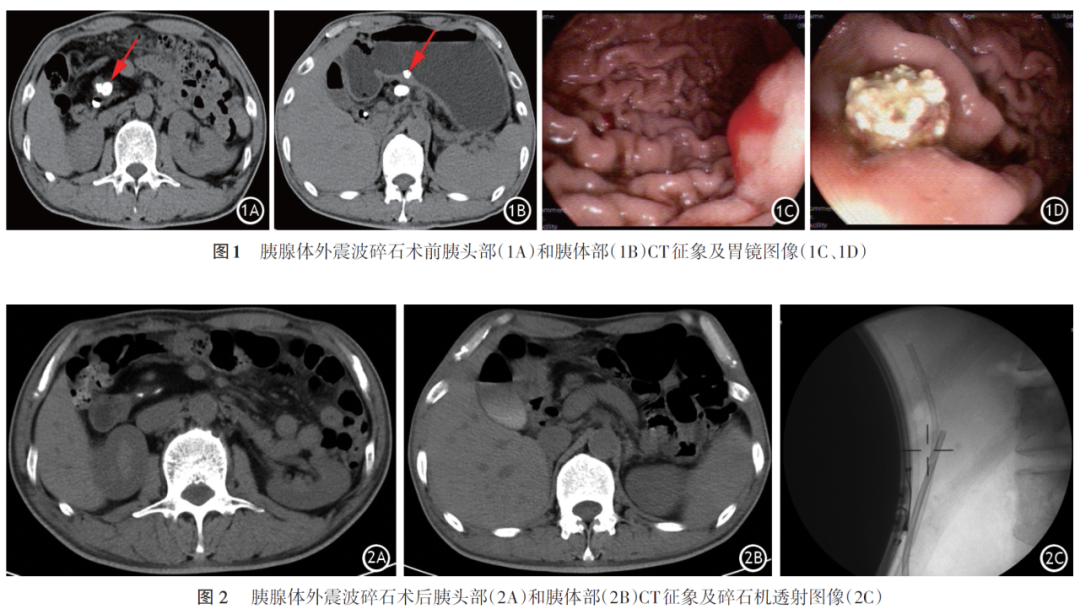

患者男,52岁。因“上腹部疼痛反复发作2月”入院。2月来患者无明显诱因反复发作中上腹疼痛,当地医院诊断为慢性胰腺炎(CP)合并胰管结石。1月前因胆总管中下段结石伴扩张于外院行逆行胰胆管造影术(ERCP),术中发现胆总管扩张并中下段多发充盈缺损,胰管扩张及主胰管内多发充盈缺损,行胆管取石并置入胆管支架,胰管结石因较大无法取石,留置胰管支架;同时发现胃体中部后壁一巨大隆起,顶部凹陷并见白色黏液附着,冲洗后仍见白色黏液外溢,循导丝以造影导管造影,主胰管显影,考虑CP合并胃内瘘形成。遂入上海市浦东新区公利医院消化科。体检无明显阳性体征。完善胰腺

本例患者反复发作上腹部疼痛,原因是胰头部主胰管结石阻塞主胰管,导致胰管高压。而胰体部结石使胰头部和体部之间主胰管的梗阻进一步加重,导致主胰管破裂使胰液外漏,从而导致胰内瘘形成。外院ERCP造影已经证实胰内瘘和主胰管相通;碎石术前胰腺CT可见局部增厚的胃壁内的高密度影(胰管结石经胰内瘘进入胃壁中);碎石术前行胃镜,观察到胃体中部后壁瘘口少量渗血,并见排至胃腔内的胰管结石。以上均证实存在胰内瘘。胰管结石最大径>0.5 cm,首选P⁃ESWL,碎石后联合ERCP治疗,有效清除了结石,胰液引流通畅,从而减少了胰液对胰内瘘的刺激,促进胰瘘愈合。